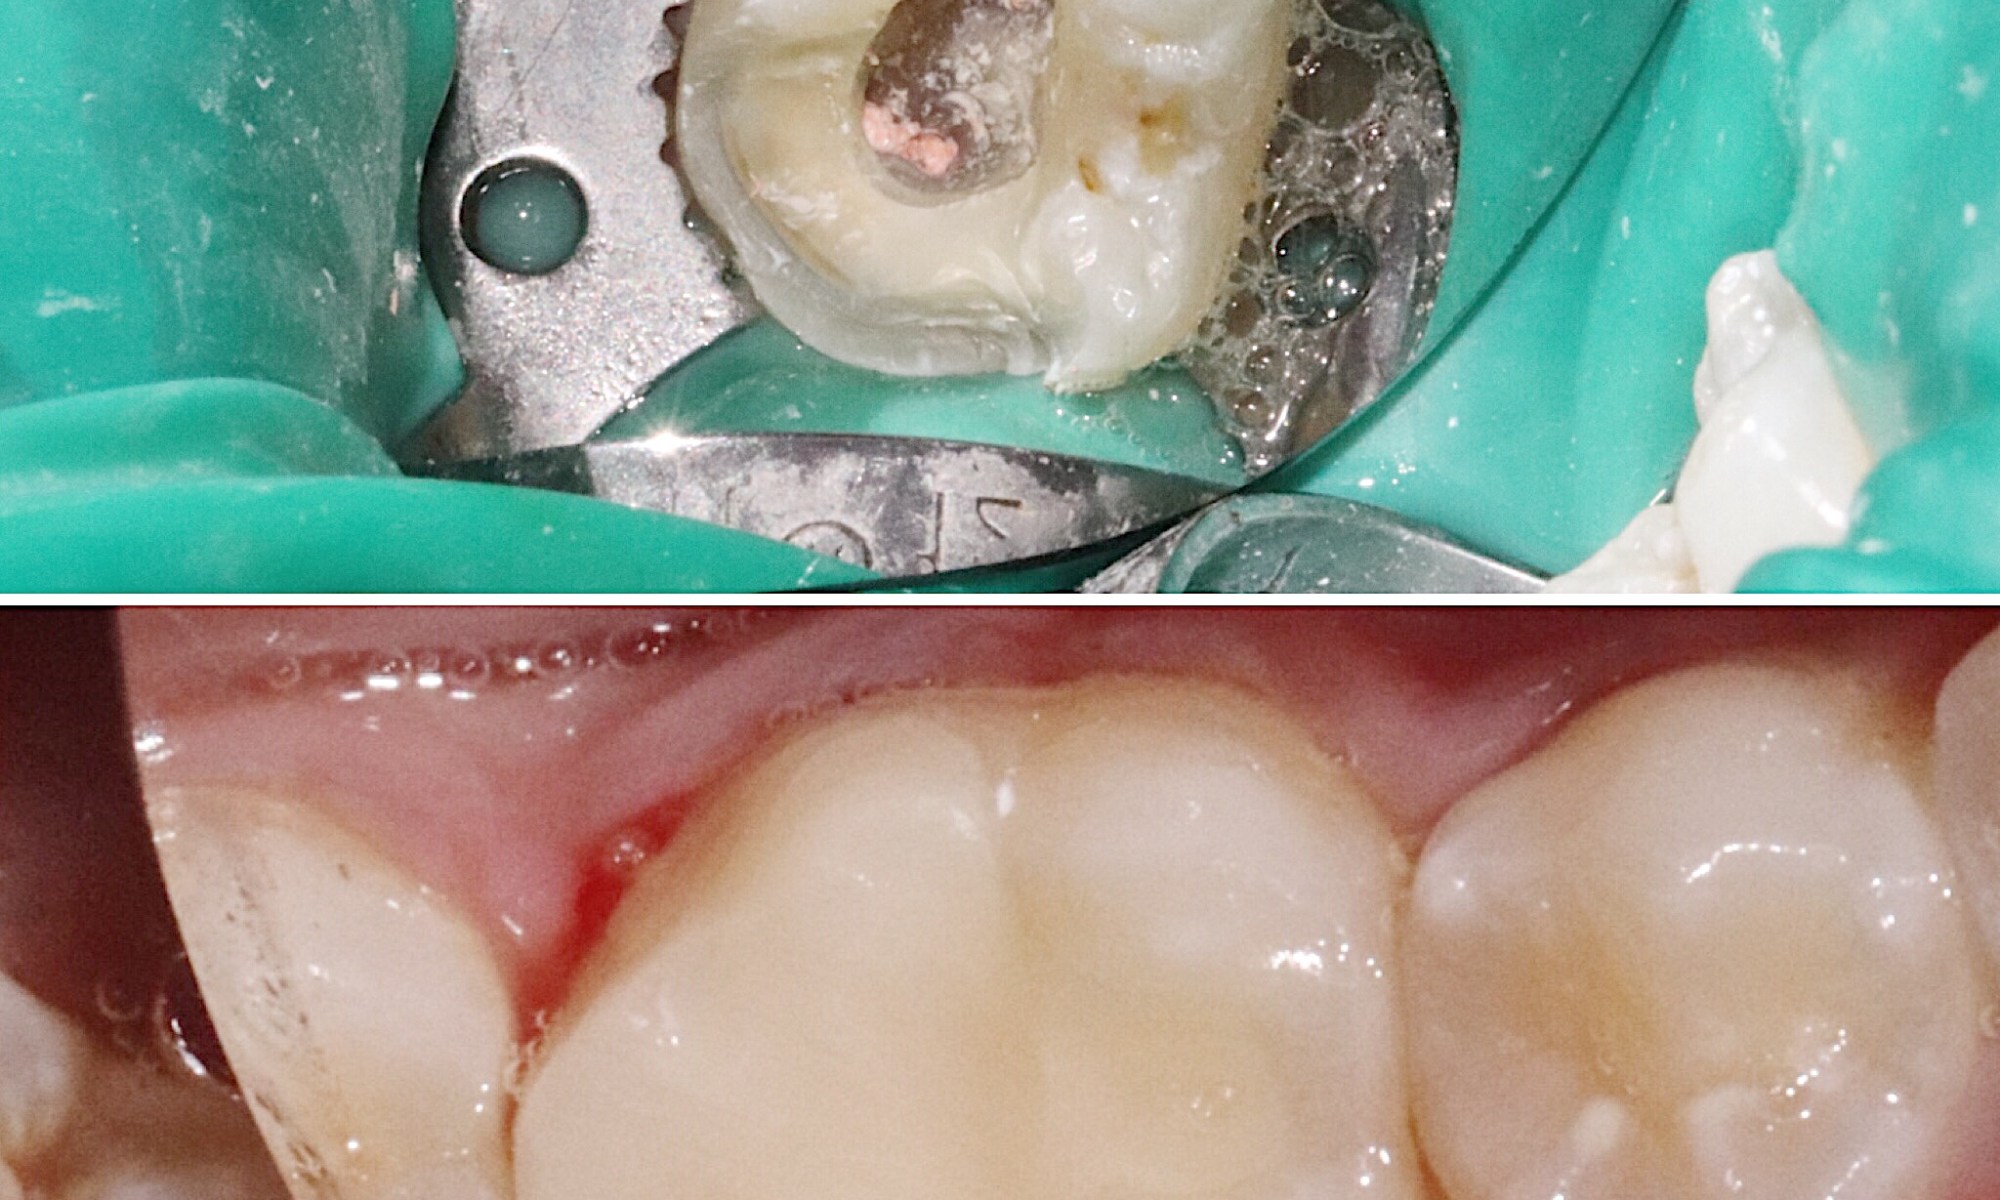

The first picture shows a tooth that just had a root canal. Notice how much tooth structure is left over. After a restoration is placed aka “core”, this tooth will need a crown for two reasons. Firstly, the amount of tooth structure left over makes it susceptible to potential fracture. Secondly, this tooth no longer has same blood supply which innately makes it very weak.